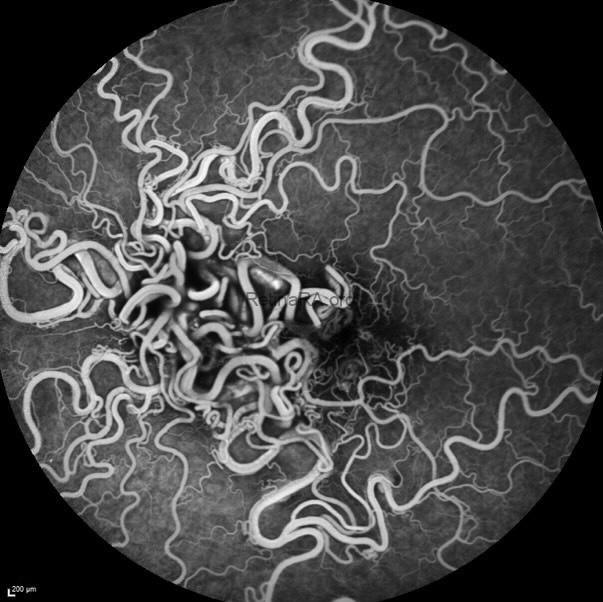

OS: Congested, tortuous vessels with a vasoproliferative-appearing lesion, highly suggestive of racemose hemangioma

FA Findings:

OS: Rapid filling without leakage, neovascularization, or ischemia